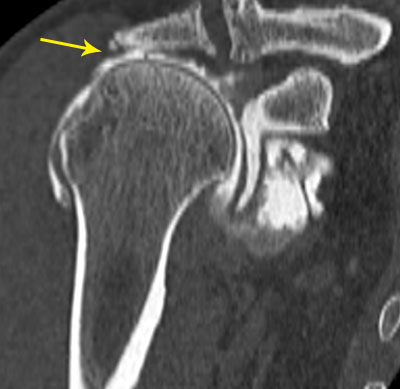

Capsulite rétractile arthrographie (images 1 et 2)

Arthroscanner correspondant (images 3 et 4)